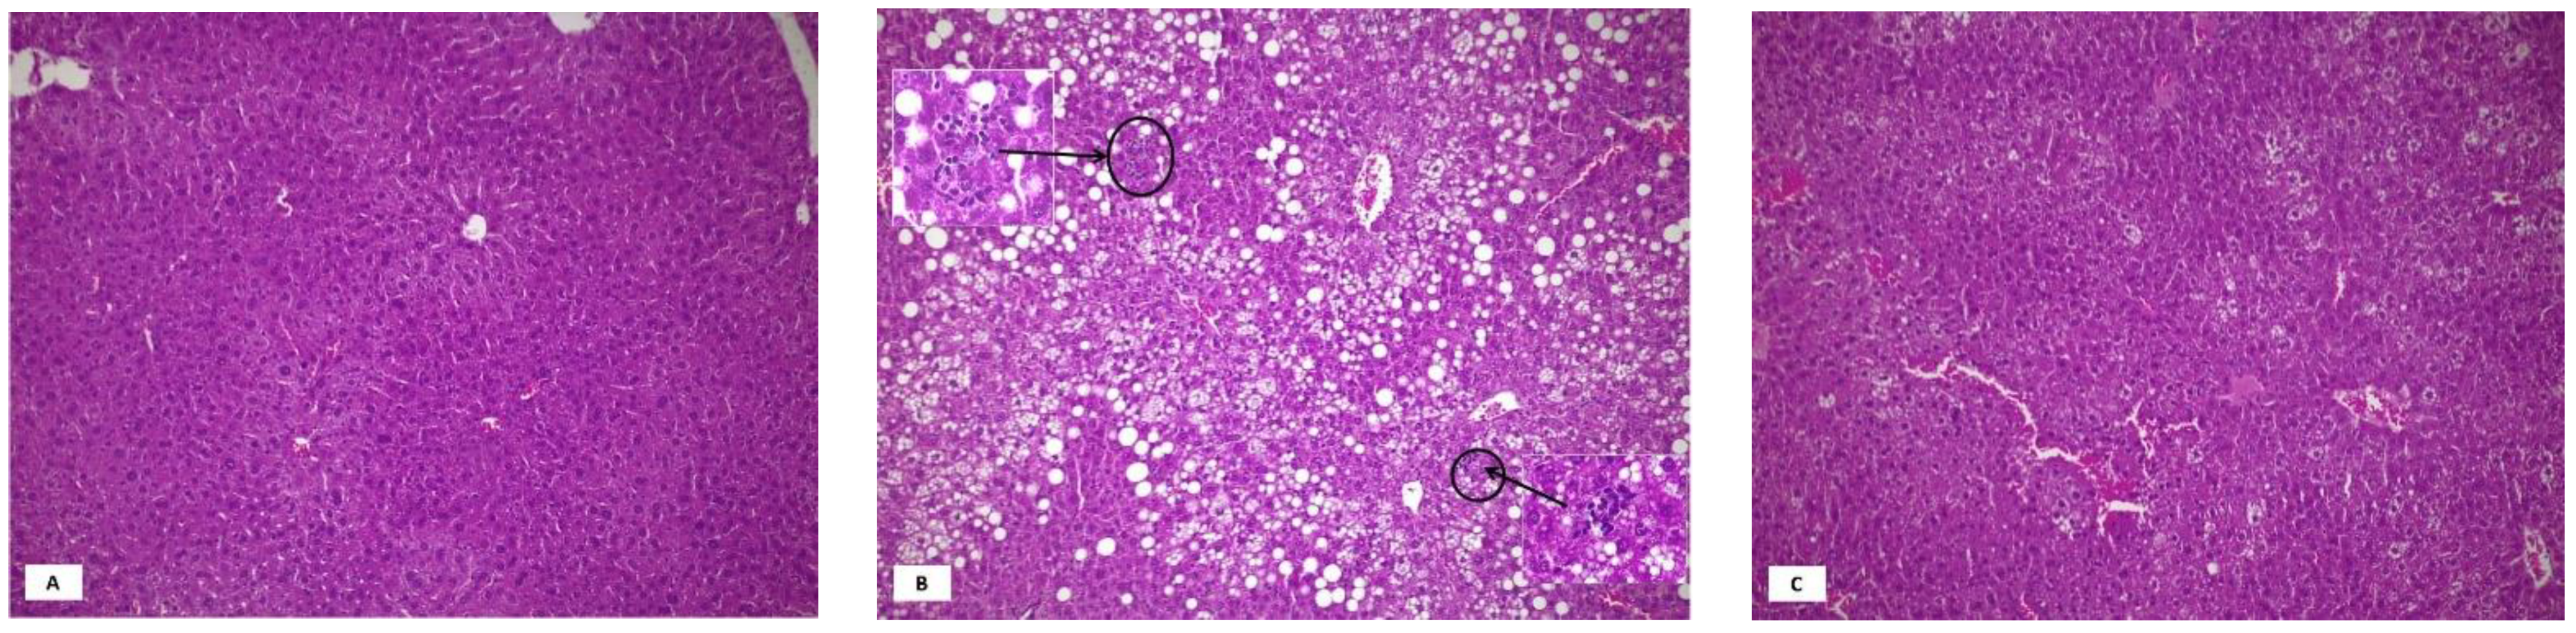

3.1. Metabolic Parameters and Liver Histology